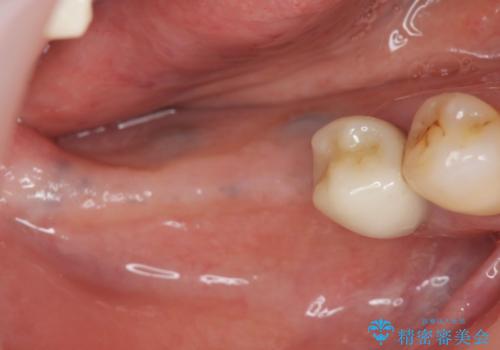

- 60代女性

- 「長年使ってきた歯を失い入れ歯を入れてみたがよく噛めない、インプラント治療を受けたい。」とインプラントt利用を希望され来院されました。